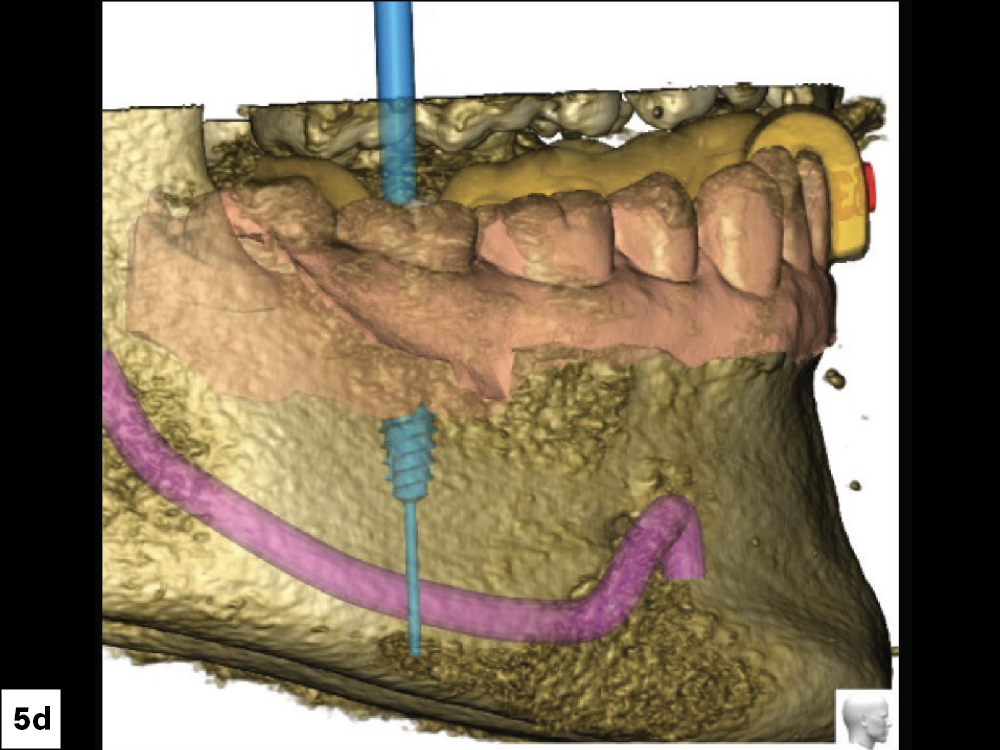

CBCT Scan (Front View)

CBCT Scan (Top View)

CBCT Scan (Left View)

CBCT Scan (Right View)

Figures 5a–5d: Treatment planning was done by Glidewell’s Digital Treatment Planning (DTP) team, which used CBCT scans to determine the ideal position of the implant.